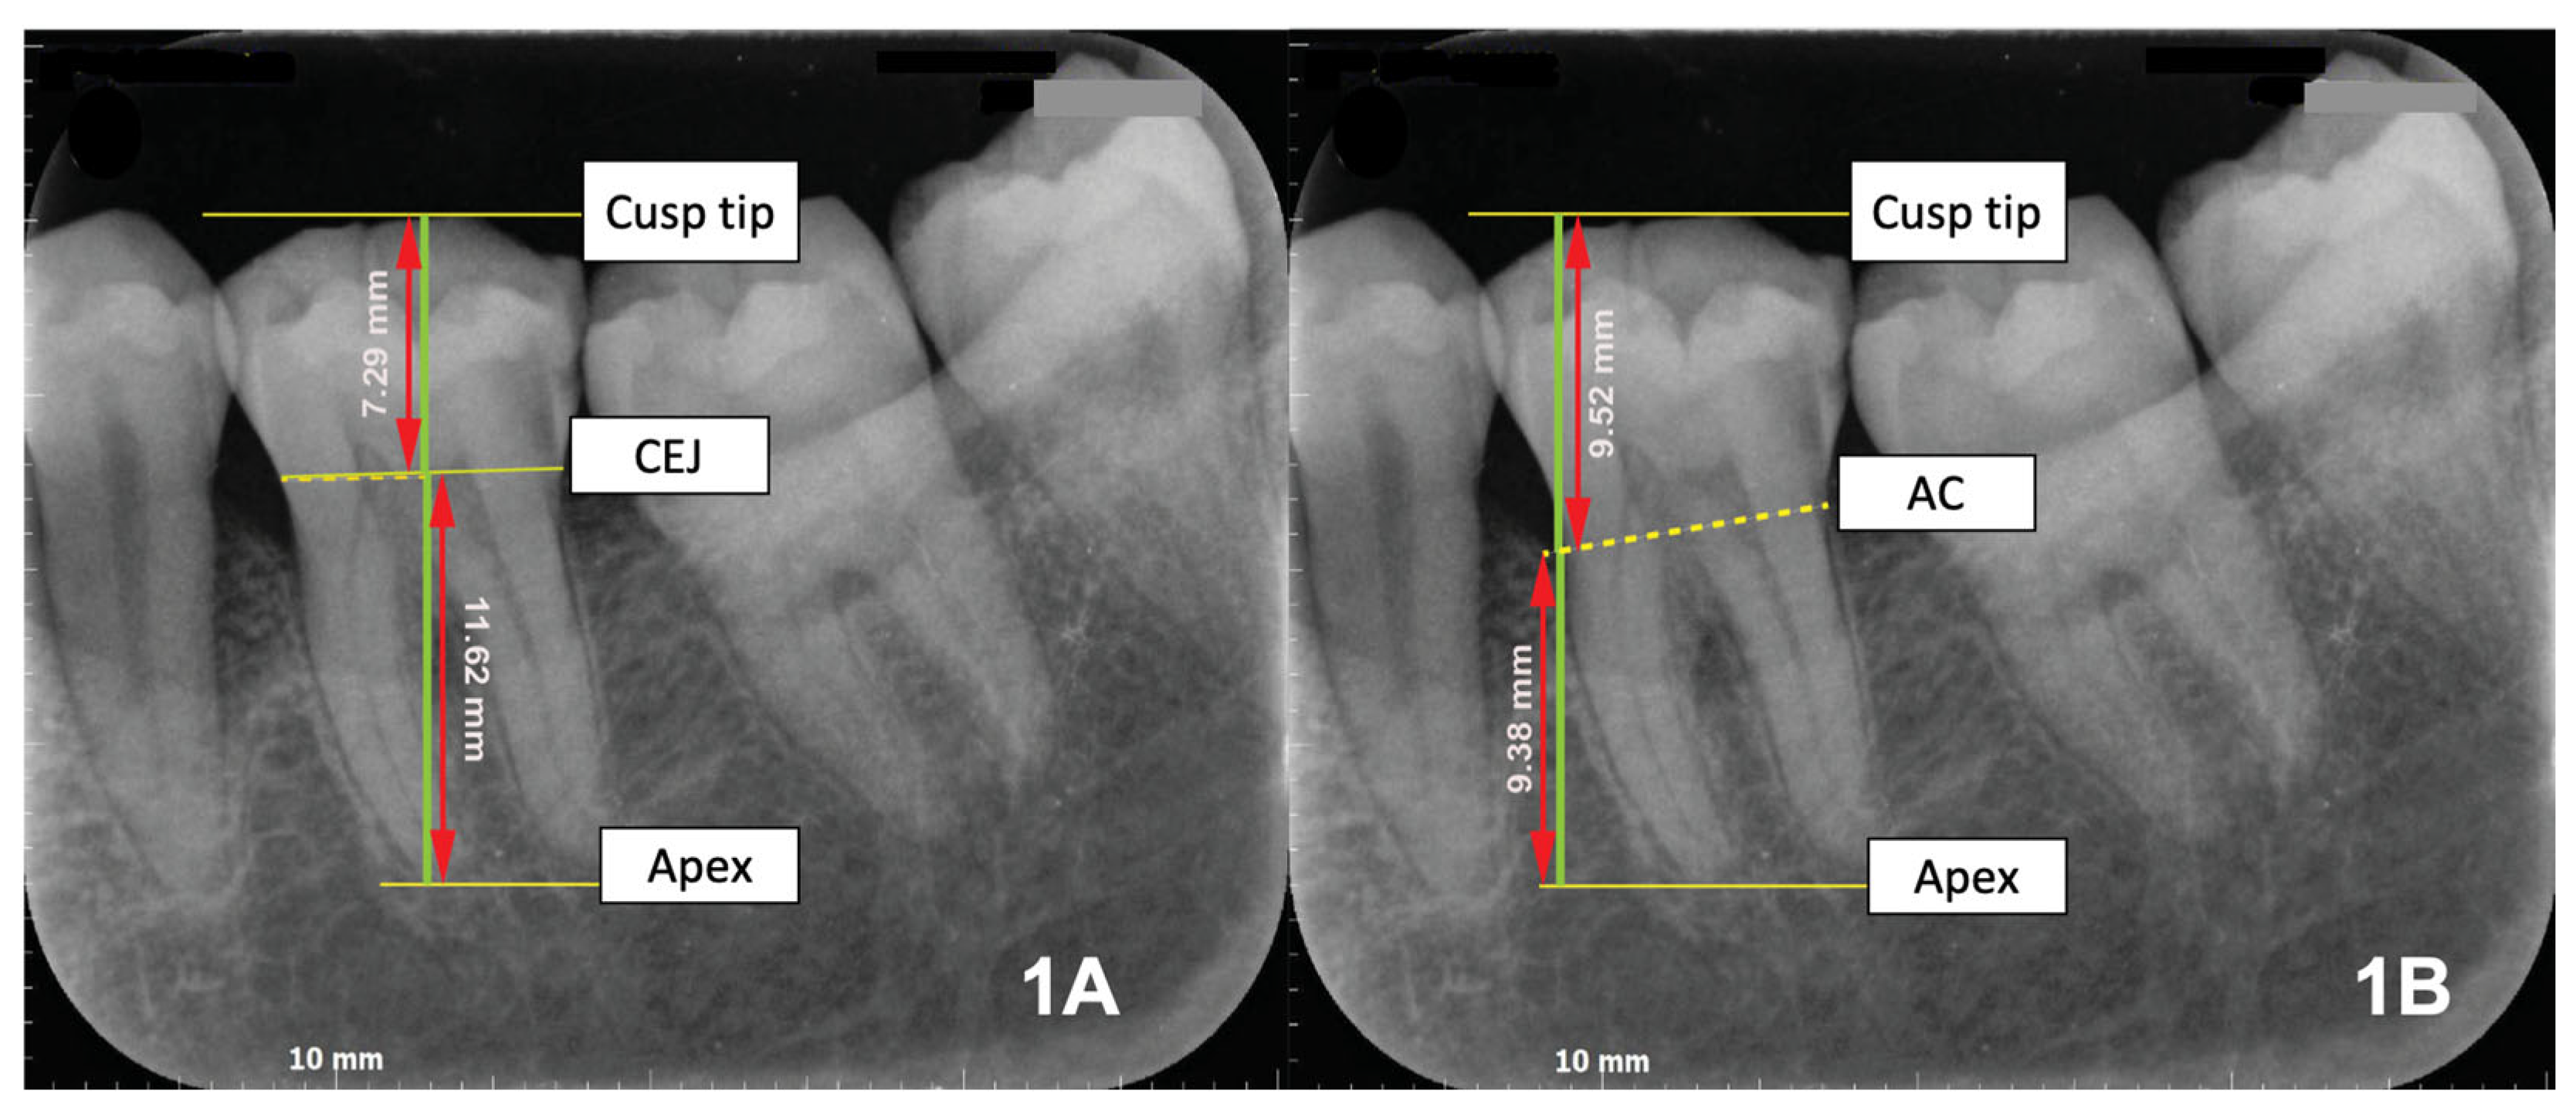

2.3. Operational Definitions and Measurements